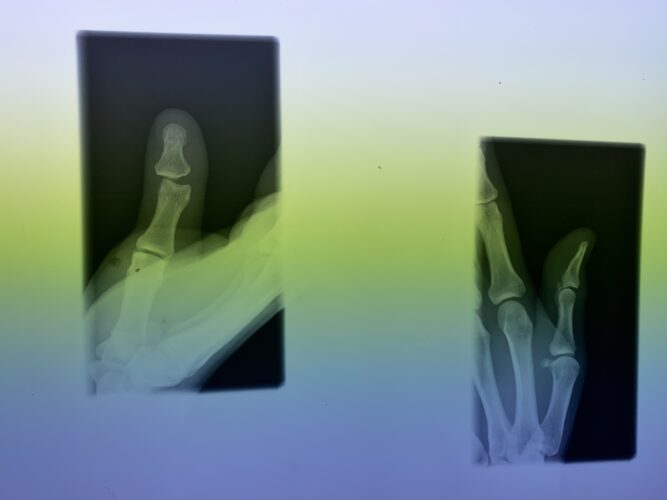

さわやか千葉県民プラザ(指骨骨折)

さわやか千葉県民プラザ(指の脱臼)